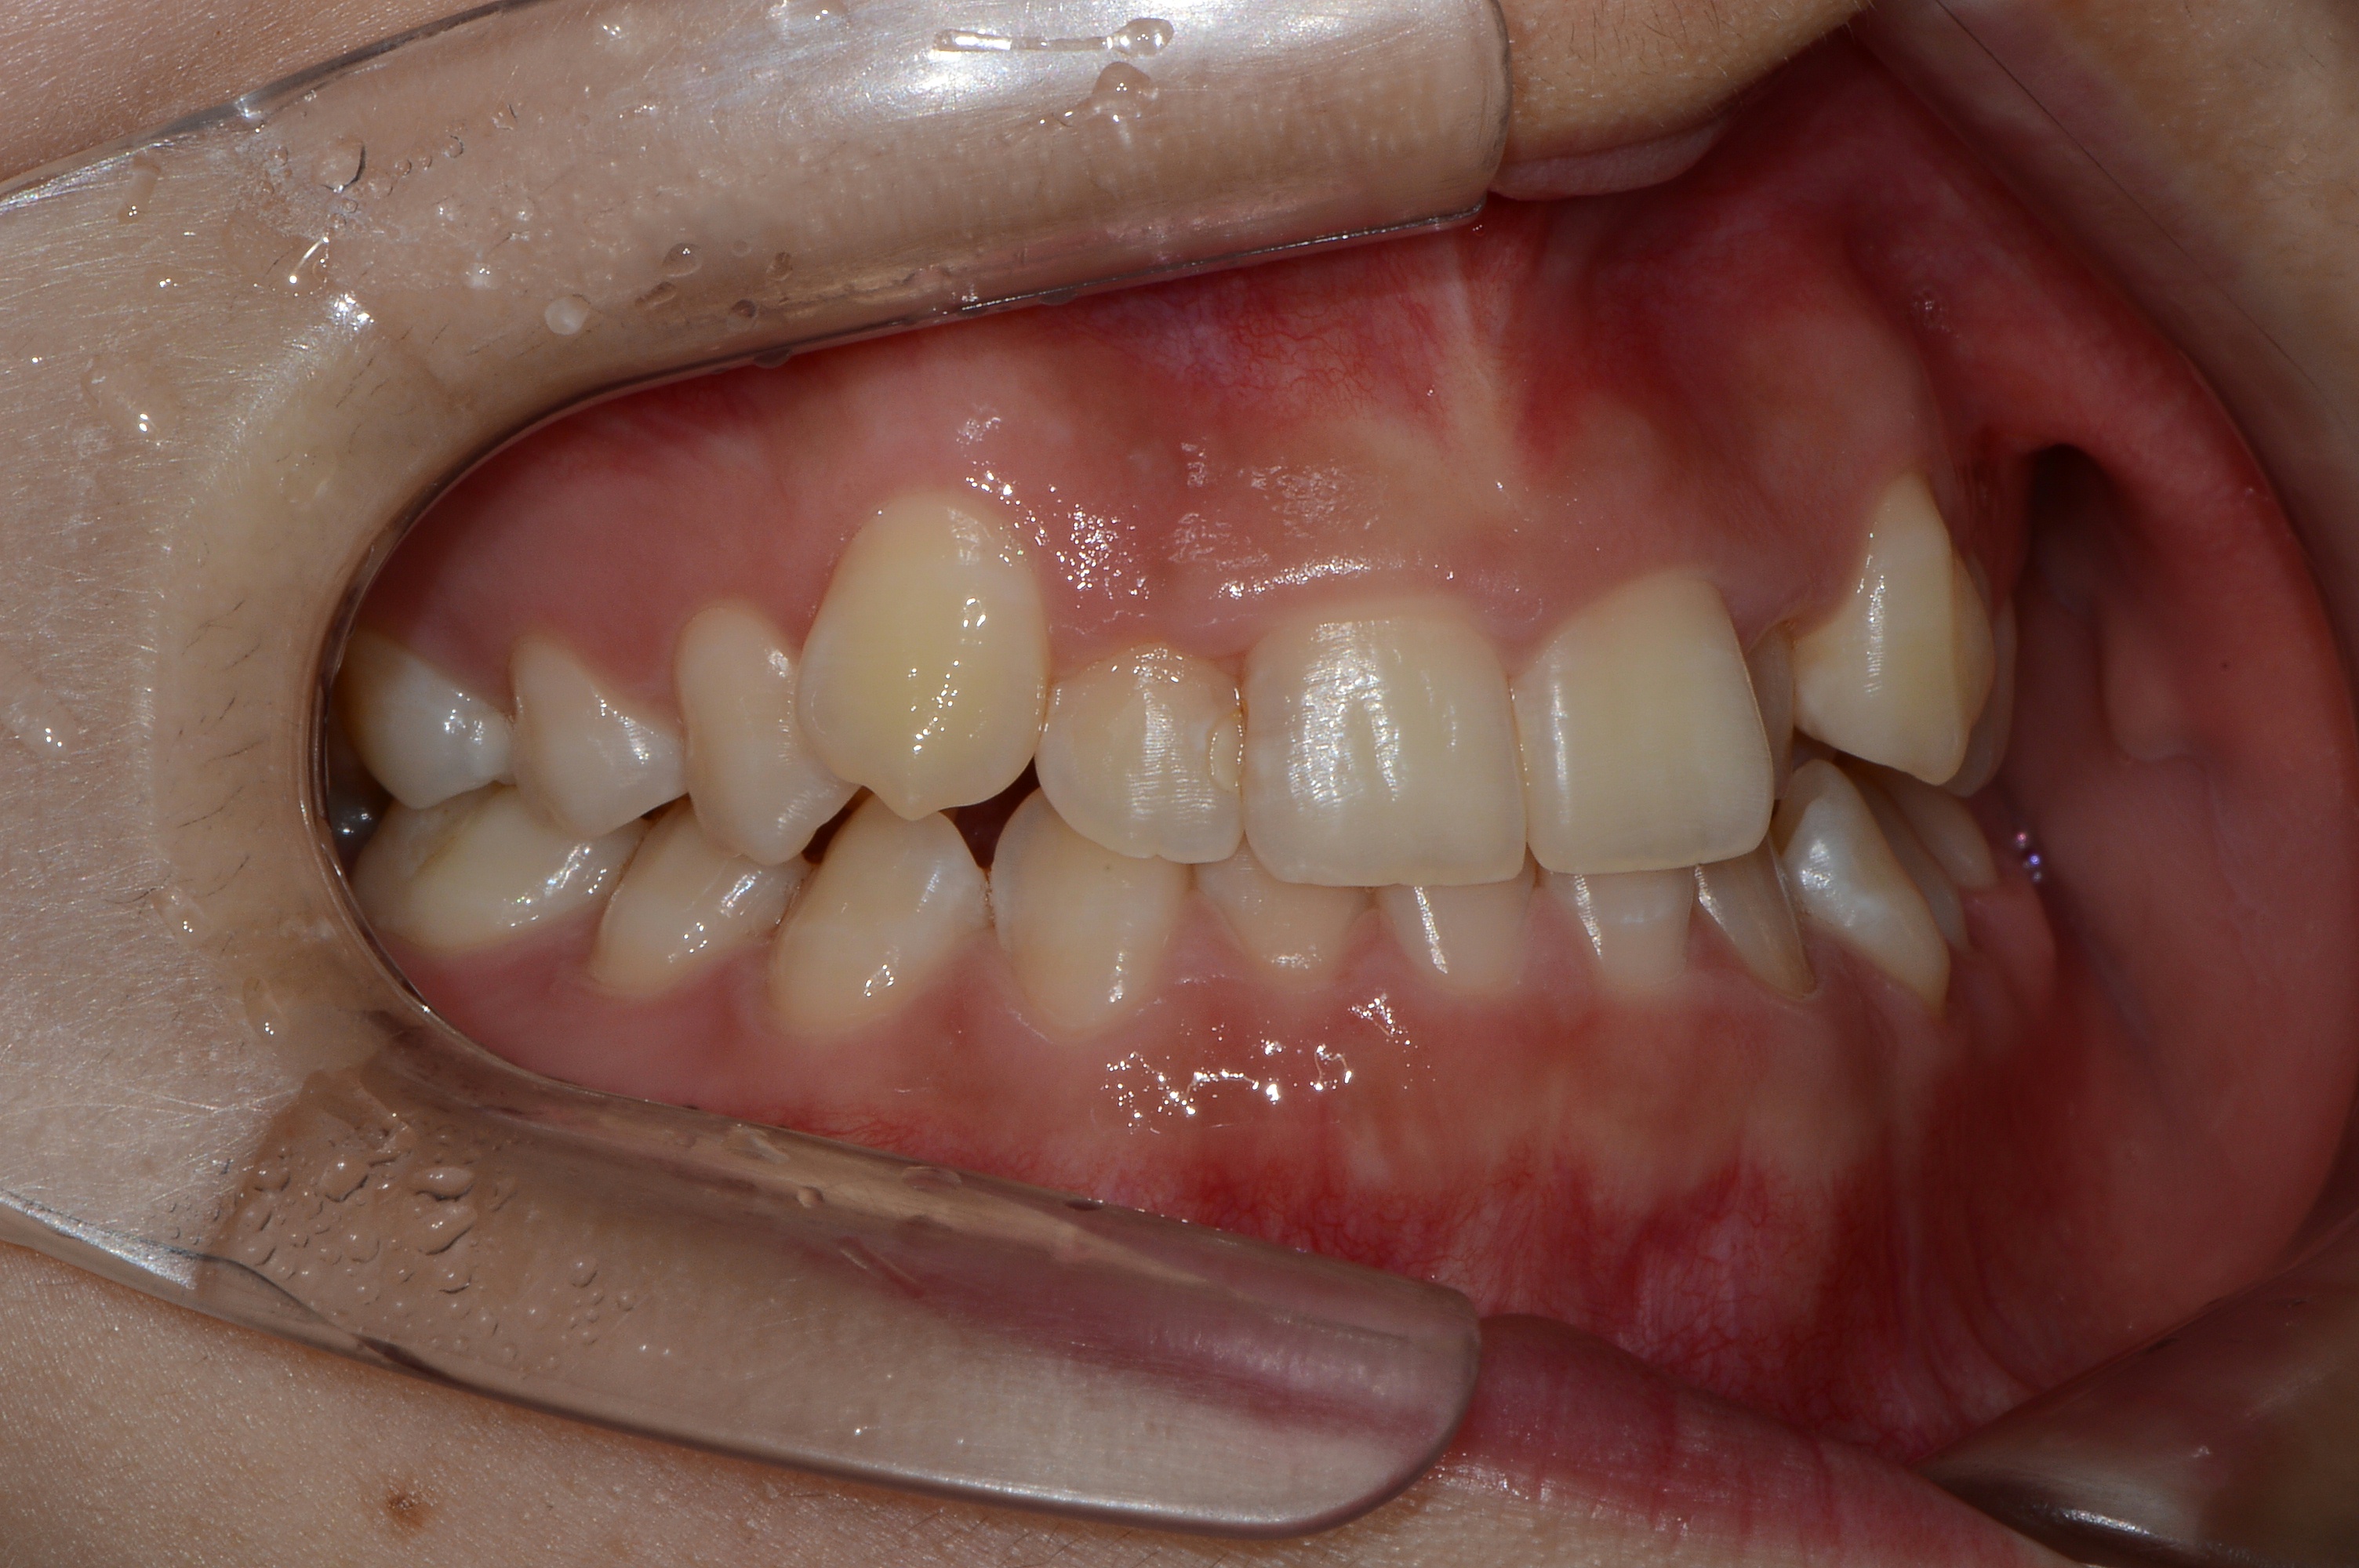

치료 전 사진입니다.